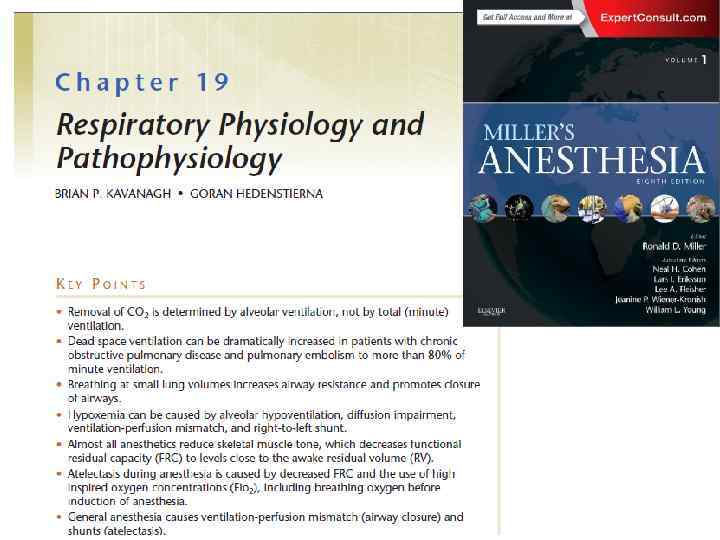

Интубация и наркоз как показание для рекрутмента

Интубация и наркоз как показание для рекрутмента

Chepter -19 Respiratory Physiology Göran Hedenstierna

Chepter -19 Respiratory Physiology Göran Hedenstierna